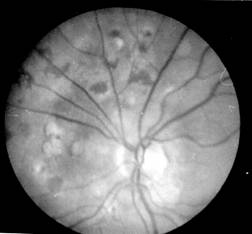

leziuni coroidiene si retiniene: buton coroidian unic sau noduli grupati cu aspect de placard alb-galbui, usor proeminent, cu contur imprecis, care in evolutie lasa leziuni cu aspect de plaje de atrofie corioretiniana alba, cu margini pigmentate. Leziunile pot fi in focar unic, multifocale, sau difuze (Fig. 12.3/4 -vezi plansa).

Fig. 12.3 - Corioretinita cicatriciala Fig. 12.4 - Corioretinita in focare multiple